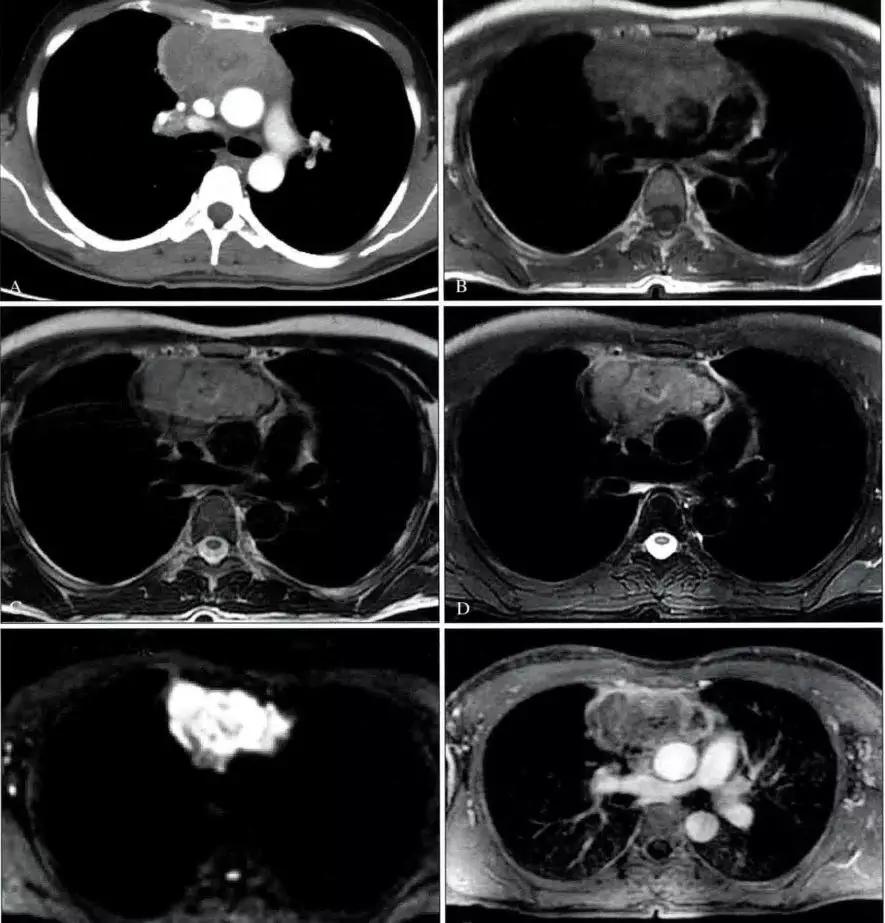

2.CT表现:前纵隔、中纵隔多组淋巴结肿大,常融合成块,尤其易累及血管前间隙组、主动脉弓旁、上腔静脉后组为最多见,易包绕上腔静脉等大血管及气管。肿块多呈均匀软组织密度,分叶状。轻到中度强化。放疗后肿块内易出现坏死、囊变、钙化灶。病人多伴有全身其他部位的淋巴结肿大。

3.MRI表现:肿大的淋巴结信号通常均匀,T1WI呈等或稍低信号,T2WI呈稍高信号。放疗后的纤维化在T2WI呈低信号,残余活动性肿瘤则为较高信号。